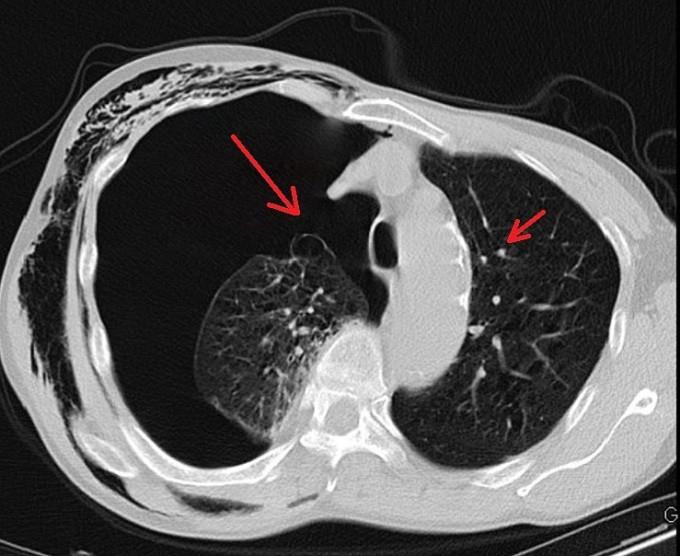

Phim chụp CT phổi của ông K. cho thấy các kén khí (điểm trắng) hai bên đỉnh và đáy phổi phải. (Ảnh: BVCC)

Sau hai ngày điều trị tại khoa Ngoại tổng hợp, tình trạng của ông K. không cải thiện, các bác sĩ chỉ định chụp CT ngực, phát hiện có nhiều kén khí rải rác ở hai bên đỉnh phổi và đáy phổi phải.

Các bác sĩ nhận định đây là trường hợp tràn khí màng phổi do vỡ kén khí, cần phẫu thuật nội soi. Điều này giúp bệnh nhân cải thiện chức năng hô hấp, vận động; tránh các nguy cơ khó thở kéo dài, tràn dịch màng phổi, áp-xe phổi, viêm mủ màng phổi.